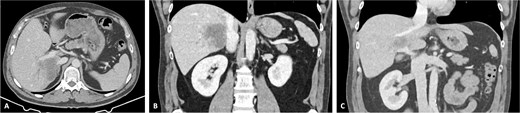

The patient was discussed at a multidisciplinary meeting for suspected intrahepatic cholangiocarcinoma. Due to the tumour size and macrovascular invasion, the patient was proposed for neoadjuvant treatment. After a biopsy confirmed the diagnosis, the patient underwent three cycles of gemcitabine and cisplatin, resulting in a reduction of the cholangiocarcinoma from the maximum longitudinal diameter of 12.6 to 7.5 cm (Fig. 2). An extended right hepatectomy with resection and reconstruction of the PV and IVC using an APFP was then proposed.

CT scan of the intrahepatic cholangiocarcinoma after chemotherapy. (A) Axial CT scan showing cholangiocarcinoma diameter reduction after chemotherapy and (B) and (C) coronal CT scan view of the vascular relation between the cholangiocarcinoma, IVC, and PV.